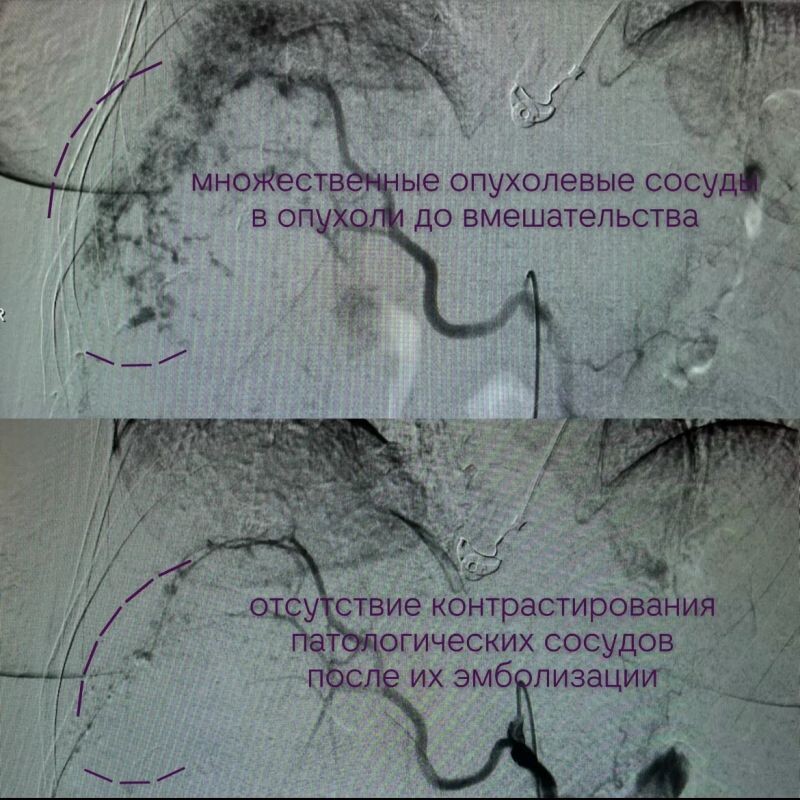

Специалисты ВОНКОЦ решили прибегнуть к проведению редкой операции. Через катетер врачи ввели специальное вещество, которое блокирует кровоток на определённом участке. В данном случае оно было нужно для избавления от новообразования.

Операция длилась около двух часов и прошла успешно. Сейчас пациентка продолжает лечение, её состояние оценивают как стабильное.